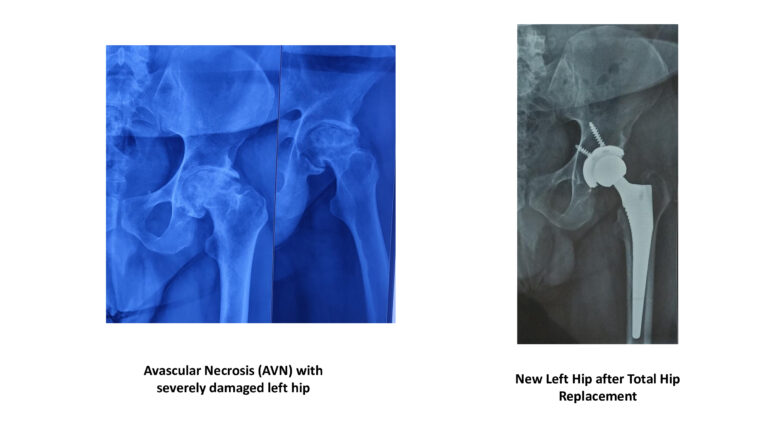

Hip Joint Replacement

I was treated by Dr Vivek Tiwari for my hip AVN problem. I was having severe pain and was not able to walk properly. Dr Vivek Tiwari did hip replacement surgery on me, after which my hip pain is completely relieved and I am able to do all my routine activities now. He is an exceptional doctor with excellent skills and is the most humble doctor I have ever met.